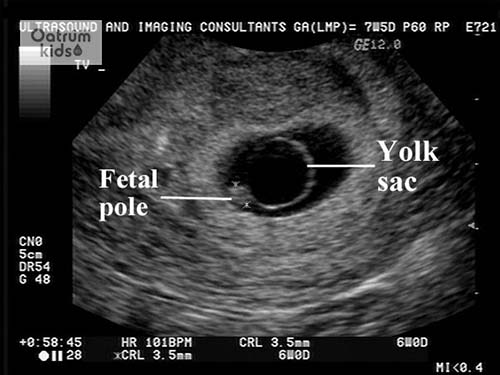

Như vậy với câu hỏi thai mấy tuần thì siêu âm thấy túi thai thì câu trả lời ở đây là tầm từ tuần thứ 5 đến thứ 6 là đã phát hiện được túi thai mẹ nhé! Lúc này túi thai sẽ có đường kính khoảng 2-3 mm. Nhưng cũng tuỳ vào từng trường hợp do thời điểm thụ thai khác nhau nên thời điểm để thấy túi thai có thể xuất hiện trễ hơn một chút.

Thêm vào đó có nhiều trường hợp còn xuất hiện túi thai giả. Túi thai thật là túi thai nằm trong lòng tử cung được xác định chính xác qua siêu âm khi có Yolk sac và phôi thai… Còn túi thai giả có cấu trúc cũng gần giống túi thai nhưng không có thành phần của thai.